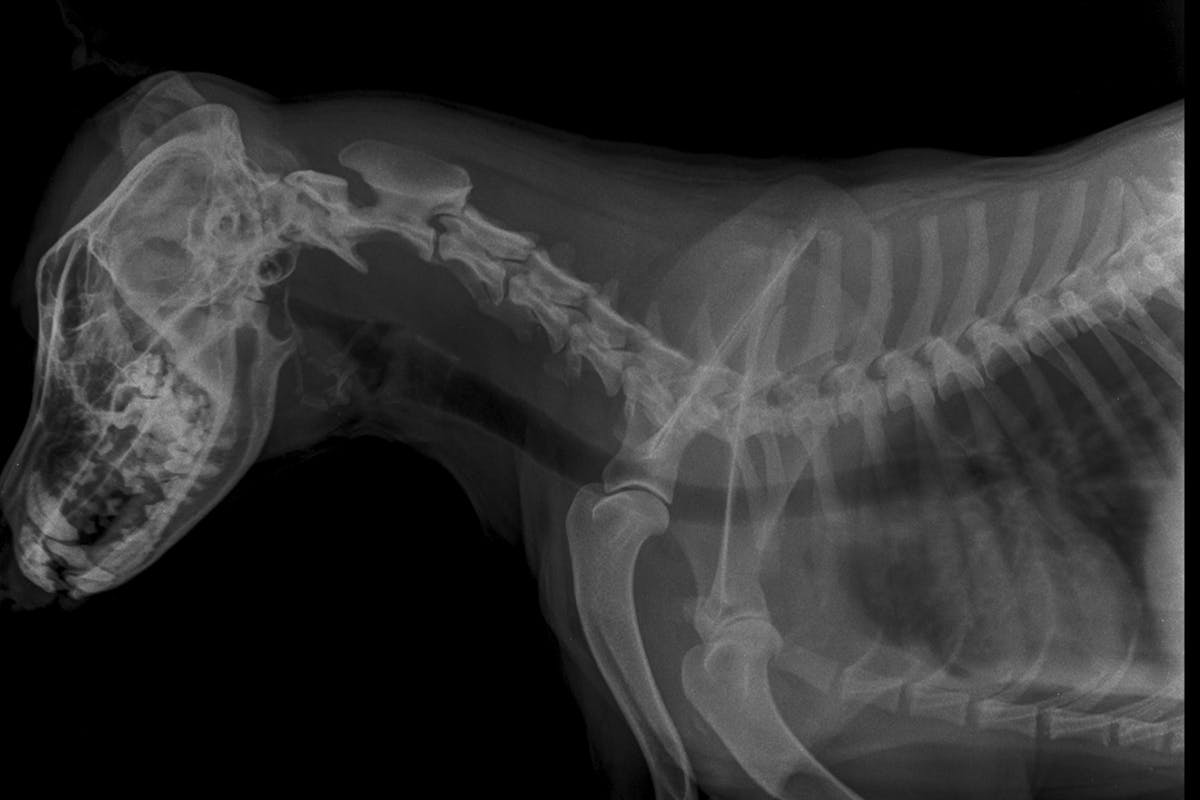

The test can be performed by a licensed veterinarian, and requires an x-ray of both the cervical and thoracic areas of the trachea. X-rays should be taken when the patient is awake and at peak inspiration.

A Board Certified Radiologist will review the x-rays, subjectively evaluating tracheal size and uniformity. They also provide an objective evaluation based on the ratio (TLR) of the tracheal lumen diameter at the thoracic inlet to the width of the proximal third rib.

If dogs are at least 12 months of age, have a normal evaluation of the tracheal size and uniformity, and a TLR greater than or equal to 2.0, they can receive an OFA certification and number. Indeterminate cases will be reported as equivocal, and abnormal cases will be reported as hypoplastic.